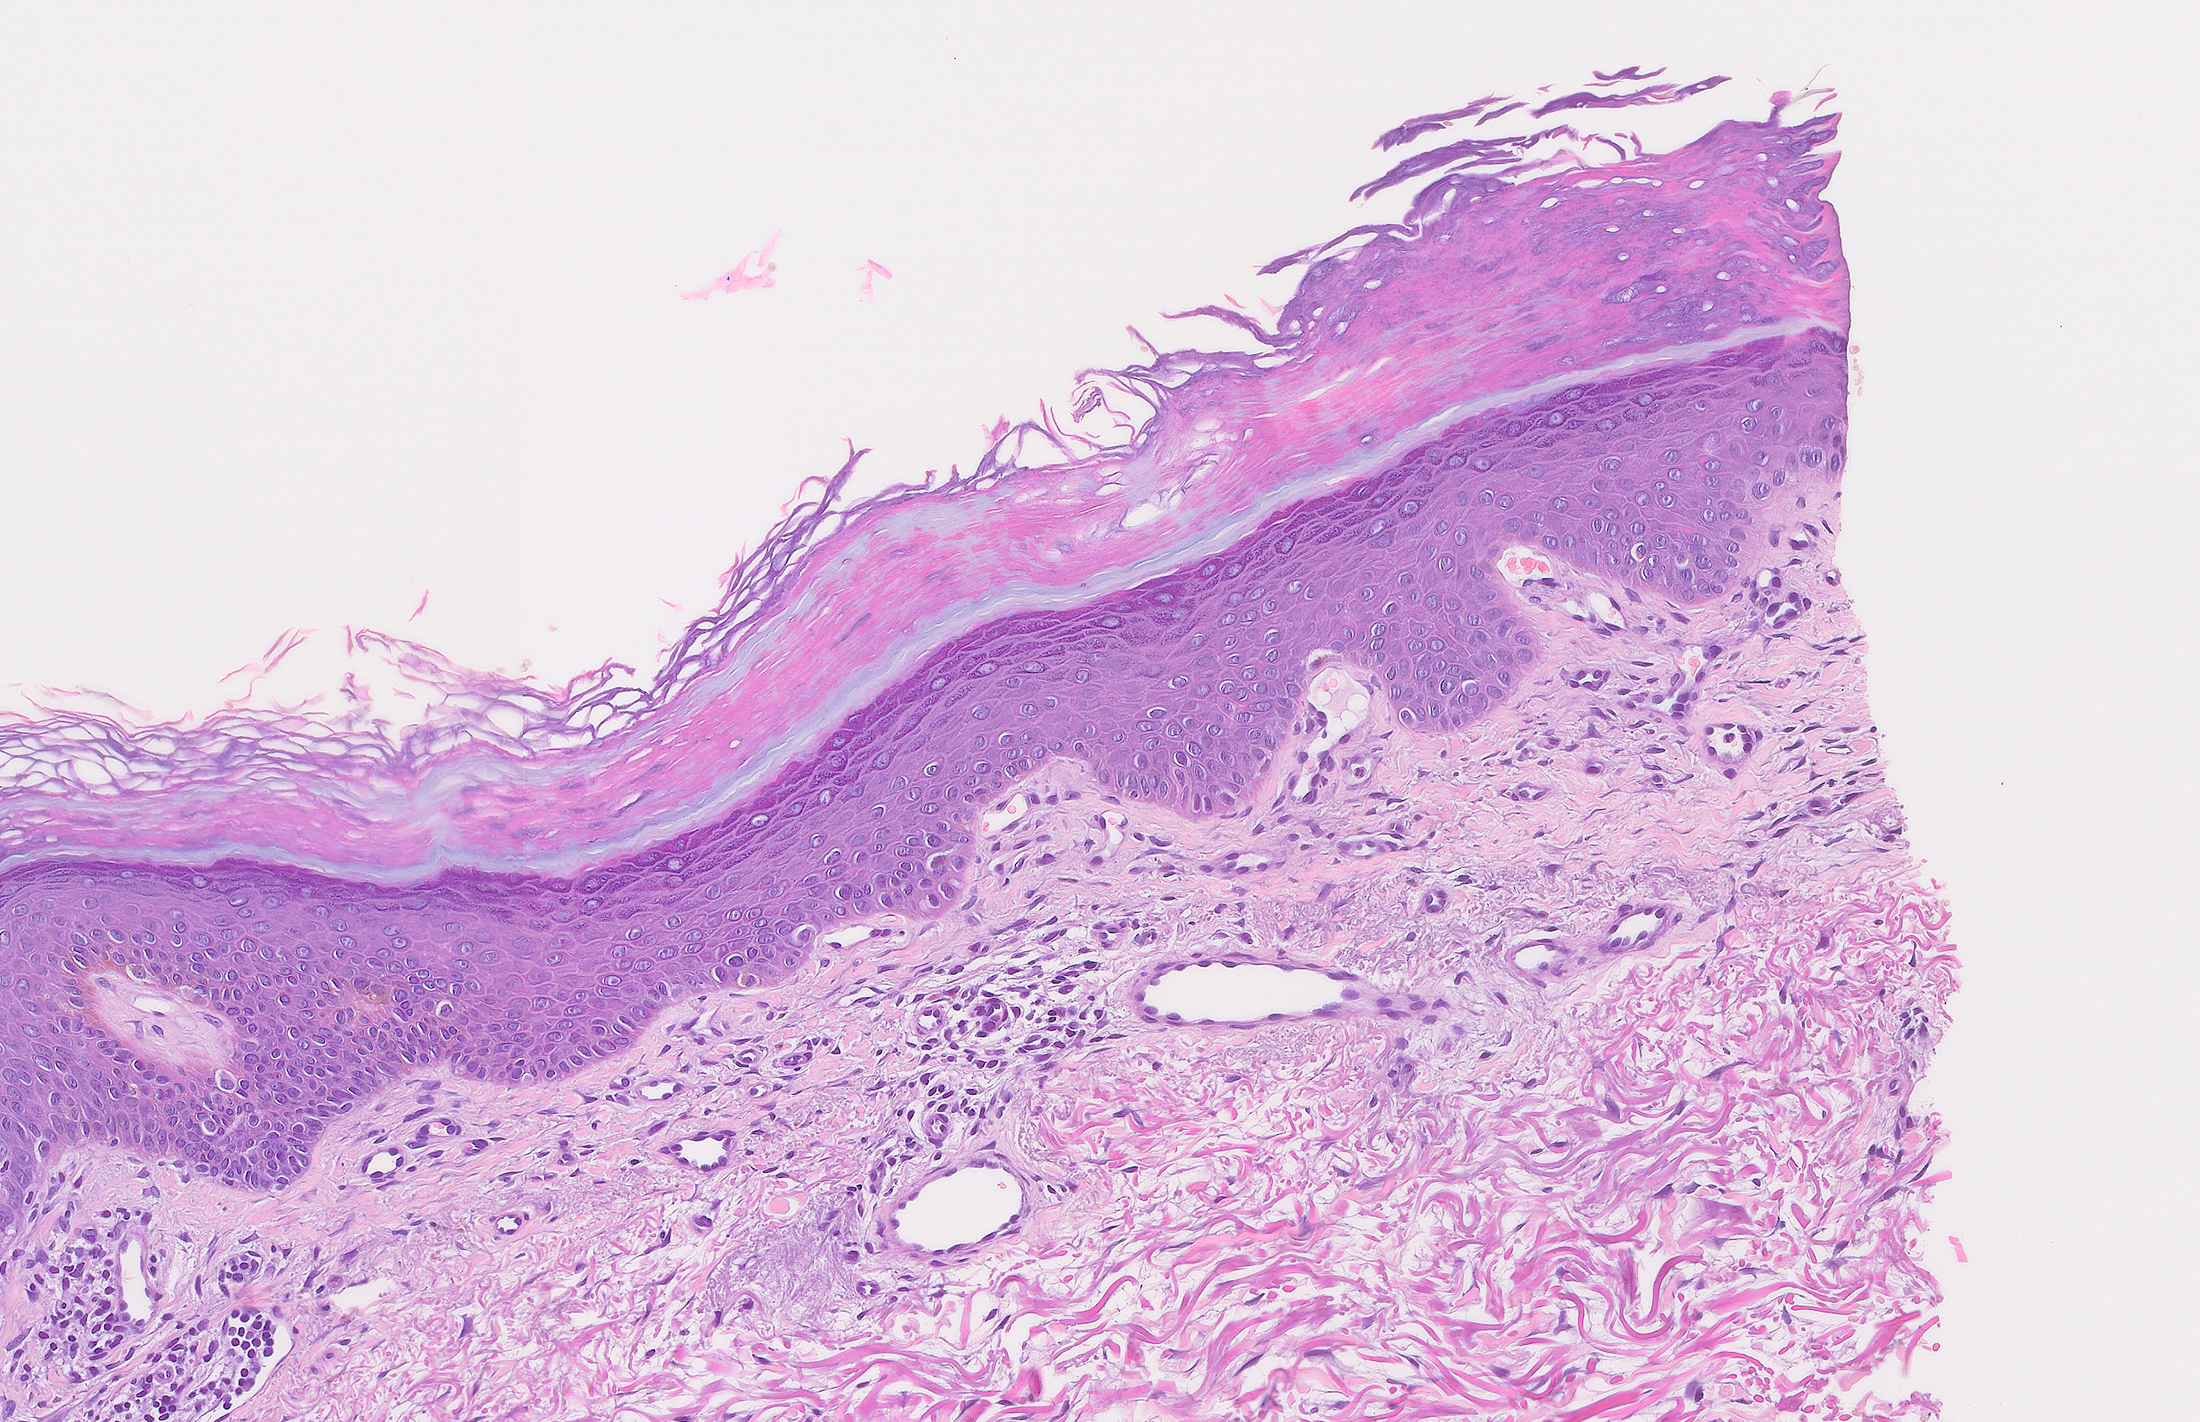

• Histología: Se practicaron dos biopsias, una para histología convencional de la que se muestran los hallazgos con hematoxilina-eosina (Figuras 5 a 7), Azul-Alcián (Figura 8), PAS (Figura 9), y CD123 (Figura 10). La otra biopsia fue una inmunofluorescencia directa que mostró la presencia de cuerpos coloides intraepidérmicos que se teñían con todos los inmunorreactantes.